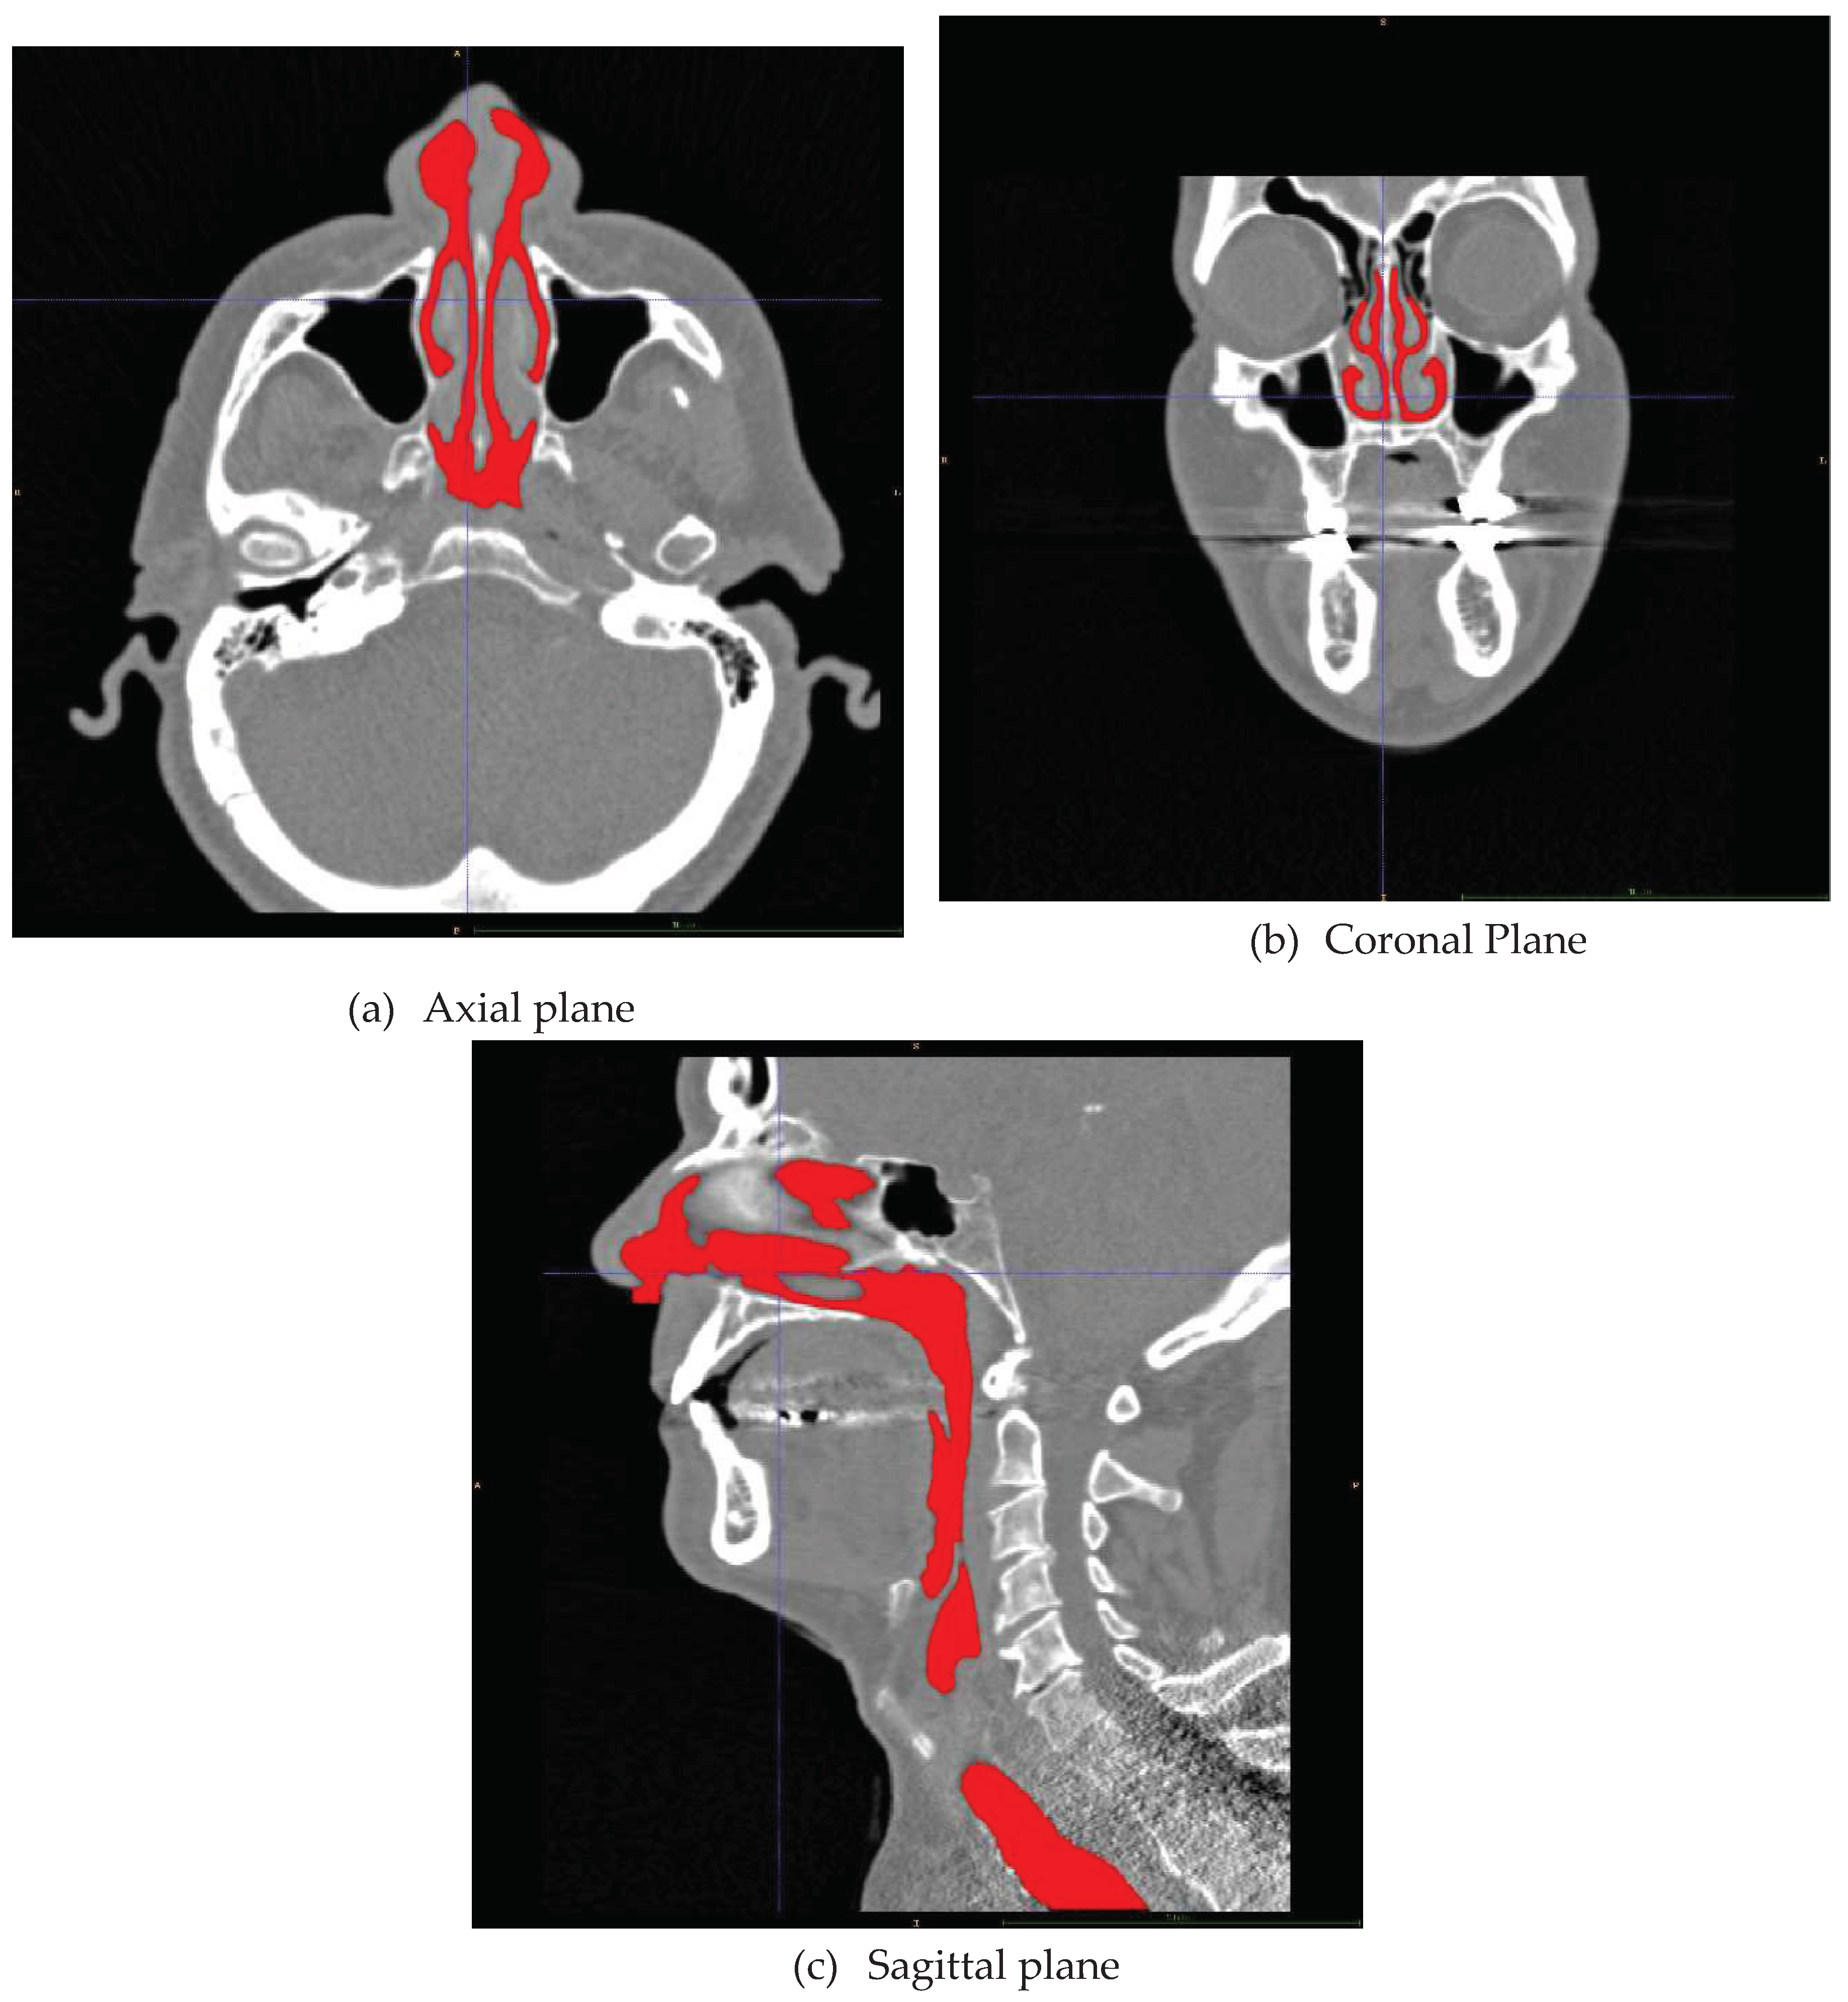

I.5.3 Acquisition and preparation of the digital airway geometry model

- Automatic segmentation methods may overlook important details or include secondary air spaces such as the paranasal sinuses, Eustachian tubes, or nasolacrimal ducts. It is recommended to confer with medical expertise such as radiology experts or surgeons to assess the resulting geometry model.

III.1.2 Geometry retrieval